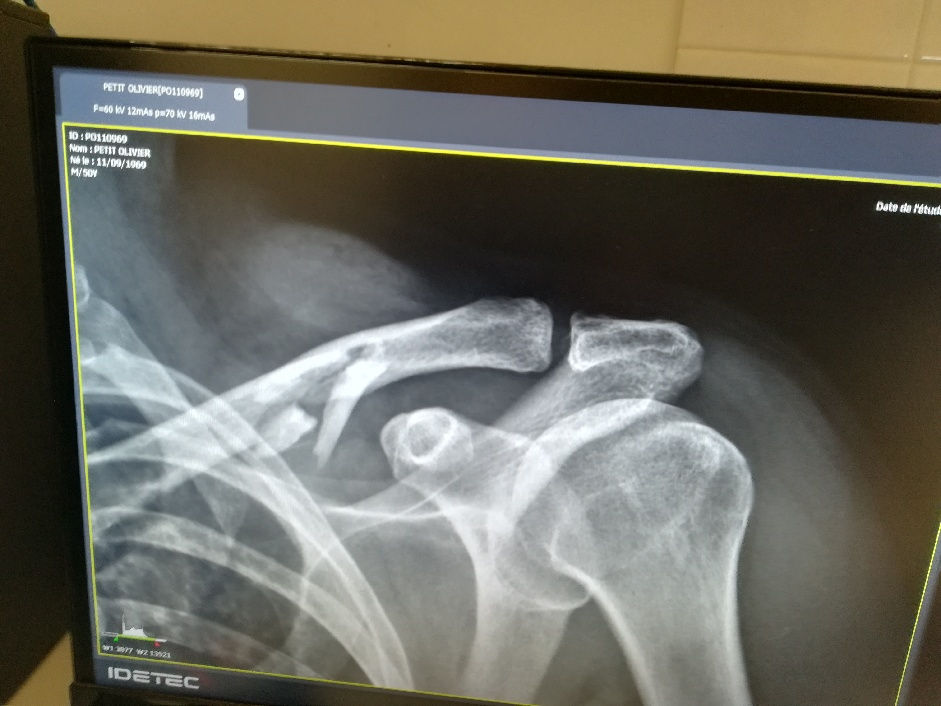

OUPS SORTIES LOUP !Oliver Small15 févr. 20201 min de lectureDésolé mais une chute à skis m'empêche d'encadrer les sorties nocturnes Loup du Mardi jusqu'au mois de mai.